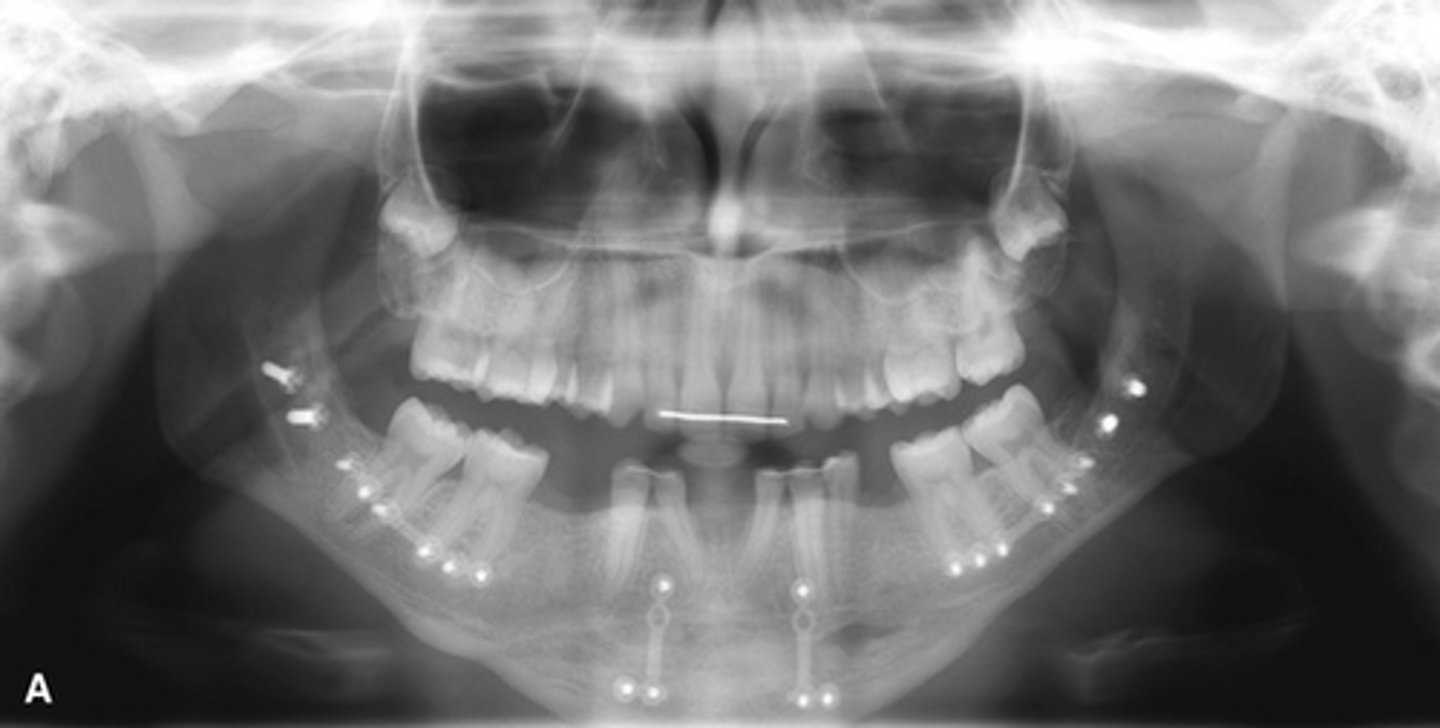

Florid Cemento-Osseous Dysplasia (FCOD)

(florid= widespread) Affects the same demography as PCOD

What dysplasia is pictured and who gets it?

Simple bone cyst; Image caption: simple bone cysts developing with florid cemento-osseous dysplasia. The scalloping feature around the roots of the molar teeth in the right mandible is very characteristic of simple bone cyst

________ is commonly associated with this dysplasia pictured.